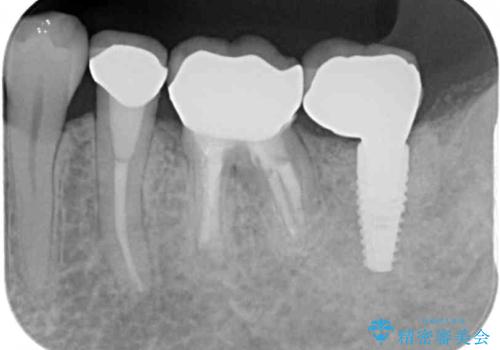

インプラント埋入にあたり、歯槽骨での炎症が広範囲であったことから、事前に骨造成を行いました。

歯槽骨の高さや幅を回復することができ、望ましい位置にインプラントを埋入することができました。